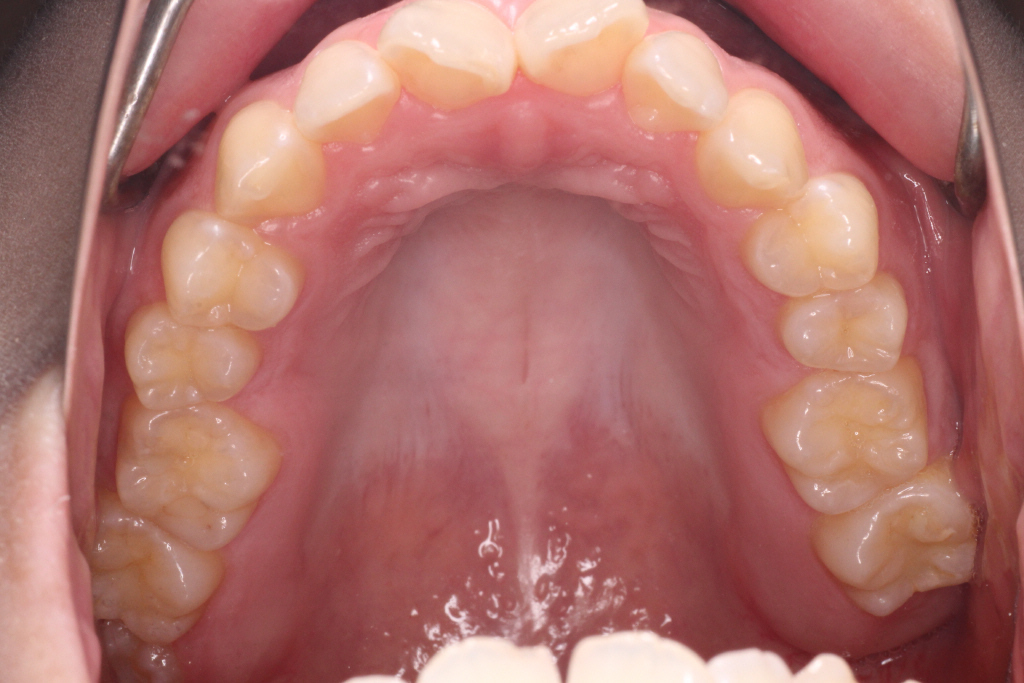

初診時の状態です。

初診時の奥歯の噛み合わせは上の歯と下の歯が1歯対1歯で噛めているので、奥歯はそのまま動かさず、

ねじれている前歯を動かしていきたいのですが、スペースがないので、そのスペースをつくらなければなりません。